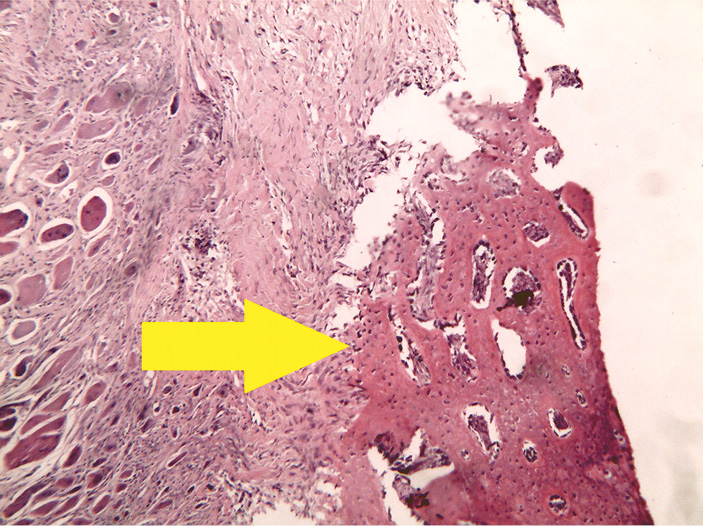

- Группа положительного контроля с использованием материала Reprobone.

В исследованном материале на 28-е сутки эксперимента отмечается крупный дефект пластинчатой костной ткани, крыла подвздошной кости, заполненный губчатым, резко эозинофильным материалом. Среди ячеек губки наблюдается выраженная смешанно-клеточная экссудативная реакция, по периферии материала преобладает экссудат нейтрофильных лейкоцитов с очагами мелкоглыбчатых распадов. В центральных и парацентральных ячейках губки экссудат преимущественно состоит из лимфоцитов и макрофагов. Между костной тканью и инородным телом виден «ободок» из грубоволокнистой соединительной ткани с очагами лимфомакрофагальной инфильтрации с примесью гигантских многоядерных клеток типа инородных тел (рис. 3). Присутствуют признаки формирования гранулематозного воспаления в надкостнице.

Рис. 3. Группа положительного контроля: губчатая структура Reprobone, заполняющая зону костного дефекта. В ячейках инородного тела — выраженная инфильтрация нейтрофильными лейкоцитами. Окраска гематоксилином и эозином, увеличение ×40